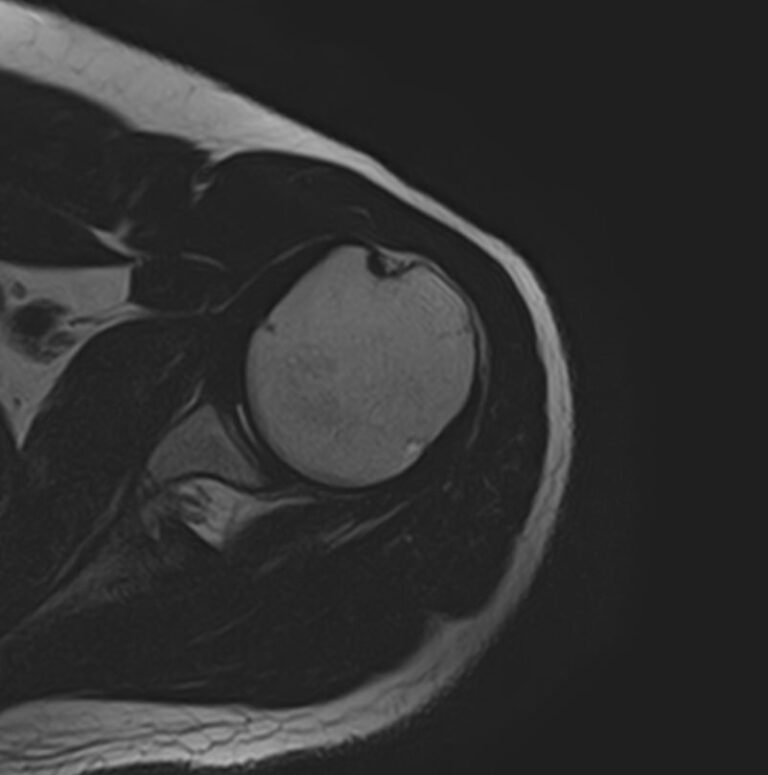

Для того, чтобы оценить состояние шейных позвонков с прилегающими тканями и одновременно визуализировать плечевой сустав, в нашей клинике выполняется комплексное обследование, включающее два протокола: МРТ шейного отдела позвоночника и МРТ плечевого сустава.

Метод МРТ позволяет оценить состояние всех анатомических областей шейного отдела позвоночника: костную структуру позвонков, спинной мозг с отходящими от него нервными корешками и окружающие мягкие ткани. Протокол обследования плечевого сустава включает оценку костной структуры, суставной капсулы, полости сустава с выстилающей его синовиальной оболочкой, связок, сухожилий, мышц и окружающих мягких тканей.